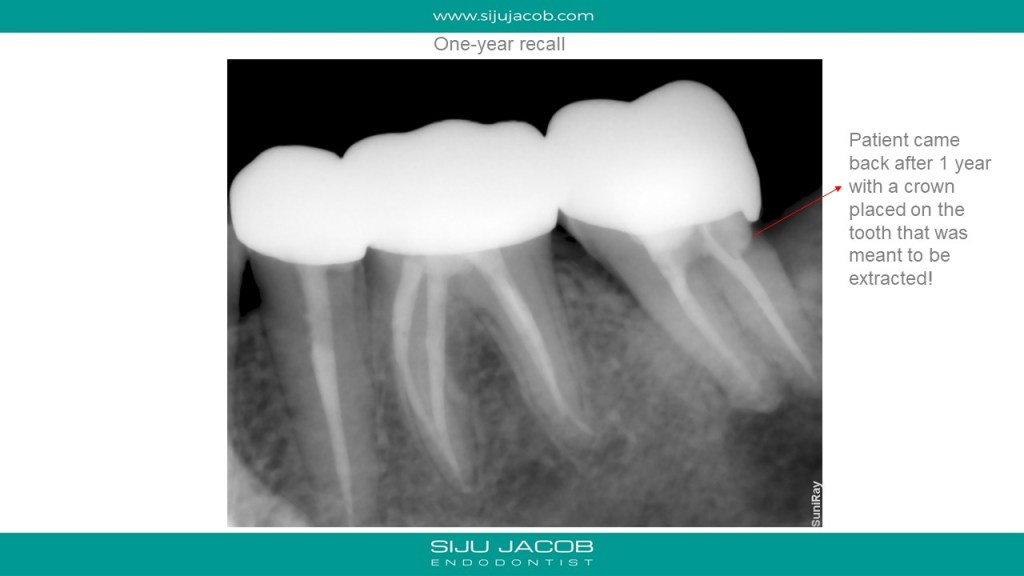

This patient came with a small swelling in relation to the first molar and carious premolar. The molar was non vital and had furcal bone loss. Most cases like these with furcal bone loss associated with a non-vital tooth usually heal with endo alone. In this particular case, I had noticed that the mandibular second molar had secondary decay under the crown and a large peri-apical lesion. I had advised extraction of the wisdom tooth and the mandibular second molar. To my surprise, the patient came back after a year with pain in relation to the second molar. I saw that the clinician had put a crown on that! I advised extraction of the second molar again. 🙂